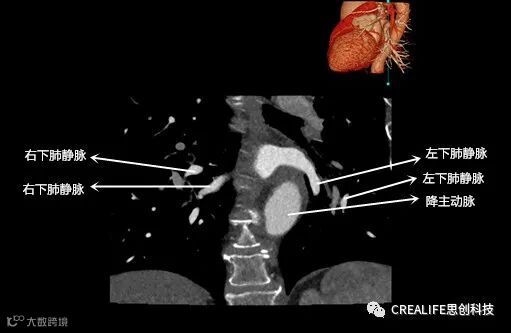

今天,跟大家分享心脏影像的经典层面——冠状位。通过冠状位的影像,我们可以从正位观察到心脏结构,看到主动脉的纵向剖面及冠窦交界处的心脏形态等多方位的心脏结构。现在,就让我们率先一睹“冠状位”的奇妙风采吧!